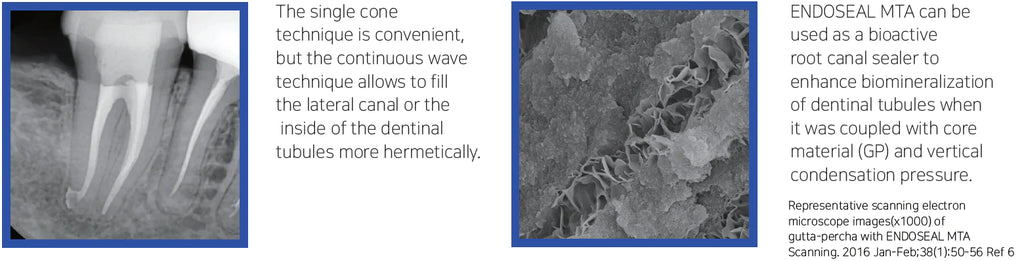

ENDOSEAL MTA is a paste-type root canal sealer based on pozzolan cement that has excellent physical and biological properties of MTA. It is premixed and pre-loaded in a syringe that allows direct application of the sealer into the root canal without requiring powder/liquid mixing, unlike other products. The product has outstanding flowability and maneuverability, which makes it possible to completely fill the root canal system including accessory and lateral canals. It is eugenol-free and will not impede adhesion inside the root canal.

ENDOSEAL MTA is developed for root canal filling and root perforation repair, effectively preventing periapical tissue irritation as well as secondary infection.